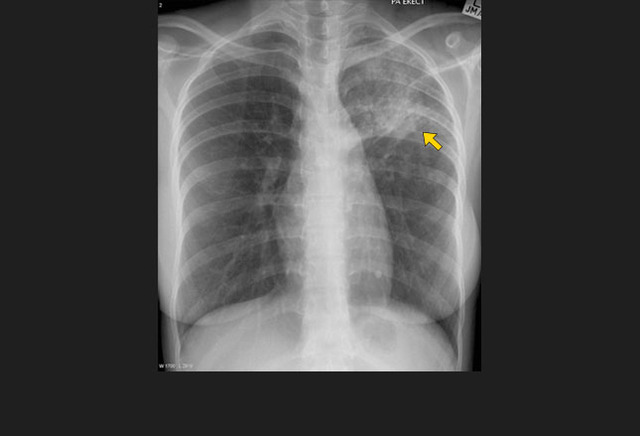

图11. 左上肺斑片状实变影,随后患者被诊断为结核

如果患者发展为对一线抗痨药物耐药的多耐药结核感染,下列哪项不是造成这种结果的原因?

A、用少于4种药物治疗;

B、在失败方案的基础上加用药物;

C、漏诊多耐药结核;

D、恰当观察下的家庭治疗;

E、之前不恰当的异烟肼治疗。

答案:D、恰当观察下的家庭治疗。